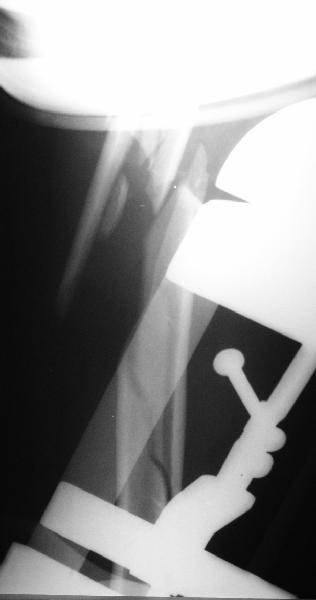

Although we can not see exactly the head piece, and assuming that there are not signs of infection, my suggestion would be to do some type of "bridging" procedure : implant fixation in head piece and distal main fragment, and the rest to be left on its soft tissue attachments (living bone graft).

I just did this attached case, using 90 degrees angled blade plate, and this would be my preference in all similar cases.

Well, to date he is still on abduction splint with traction applied to a wire placed through the olecranon. Images attached. The acetabulum

was ORIFed. The humerus is still discussing...

The views you now show demonstrate an extra articular fracture with good alignment on the AP, and some displacement on the lateral.

This should be able to be managed with adjustment of the traction.

Ilizarov is probably the best fixation if you decide to do so. However, it will heal with nonoperative treatment, with painless, reasonable

function. Even if it does not heal primarily, the pieces will heal enough to become a single level problem, readily solved with compression

plating. Jim Carr